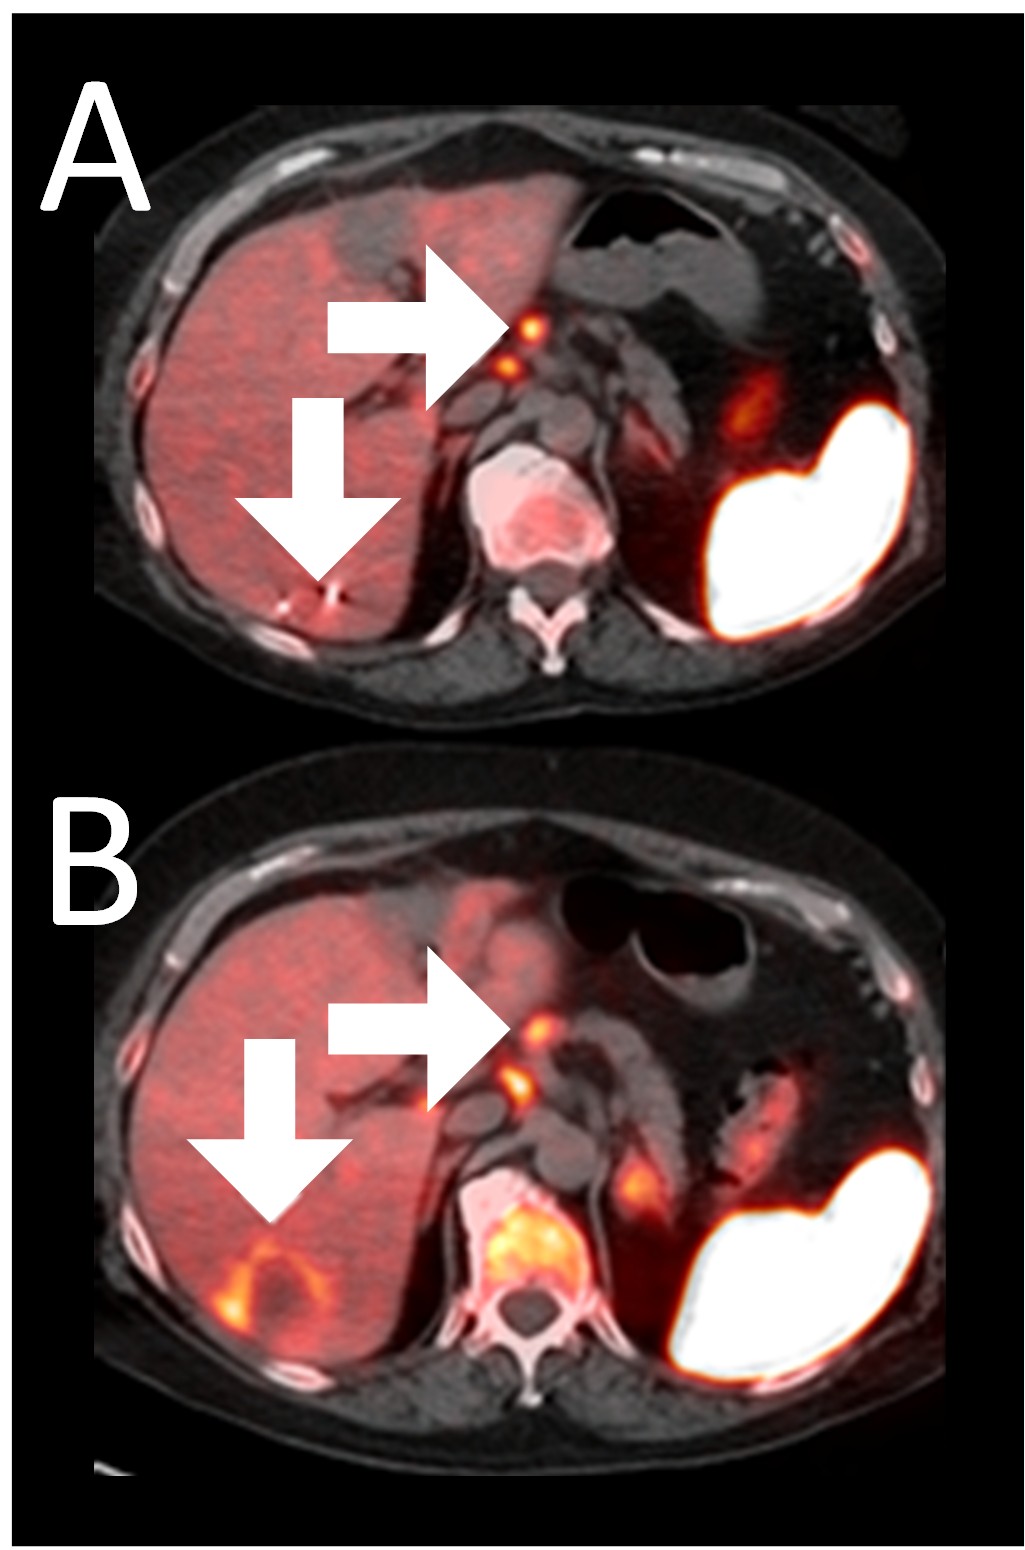

A 64-year-old woman with ER+/PR-/HER2- metastatic breast cancer, heavily pre-treated with 8 prior lines of therapy, including the antibody-drug conjugate Trodelvy, remains alive 25 months post-enrollment. At baseline, presented with hepatic metastasis.

Before BriaCell Treatment Image A: A liver metastasis (lower arrow) is “cold,” indicating minimal to no CD8+ cytotoxic T cells in the tumor while enlarged lymph nodes (upper arrow) show moderate uptake.

After BriaCell Treatment Image B: Swelling (induration) around the metastasis (lower arrow) demonstrates the liver metastasis has become “hot”, indicating marked CD8+ cytotoxic T cell infiltration while further lymph node enlargement is consistent with increased activity (upper arrow) indicating increased CD8+ T cells.

Example 3 Images (Patient 15-006): Combined MRI and CD8 ImmunoPET images Pre (A) and Post (B) Bria-IMT treatment